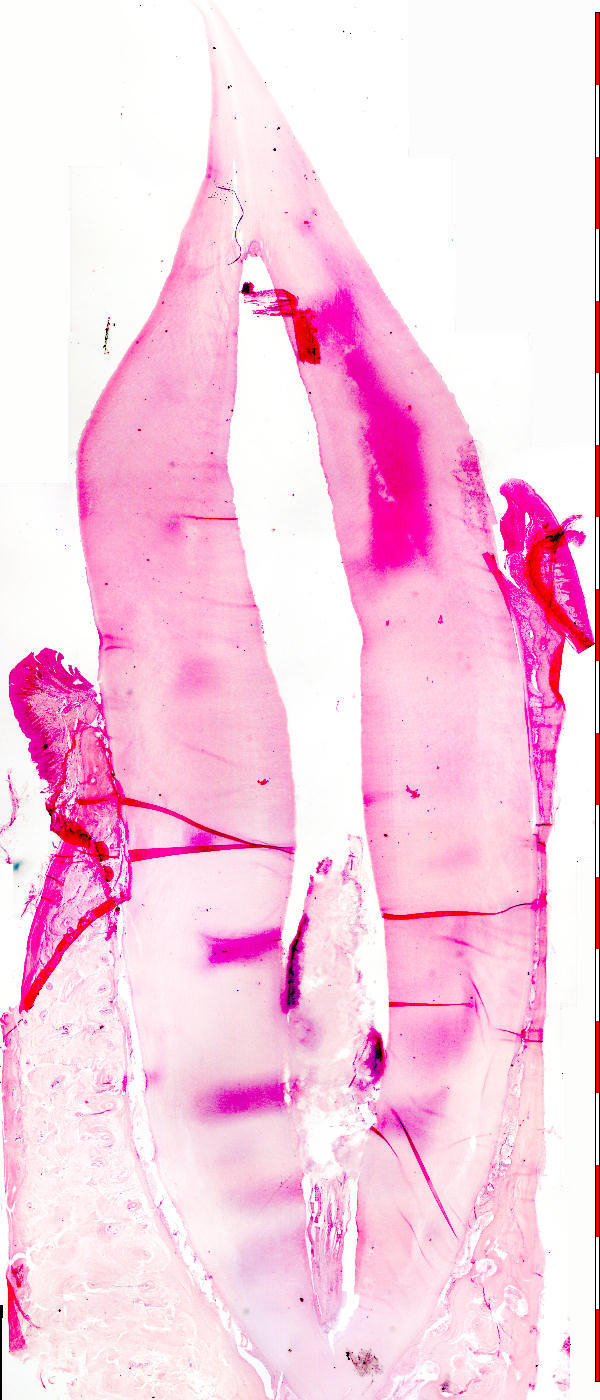

Tandsnit (lengtesnit)

Tooth (longitudinal section)